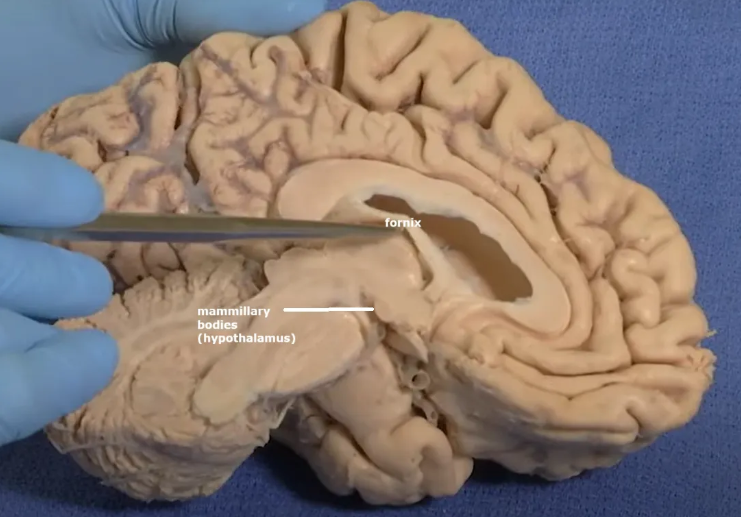

Overlaying the green cingulate and parahippocampal gyri with the purple hippocampus highlights the limbic lobe. Yellow = fornix. Brownish pink = hypothalamus

The purple hippocampus is visualized tracing the ventricular system (turquoise).